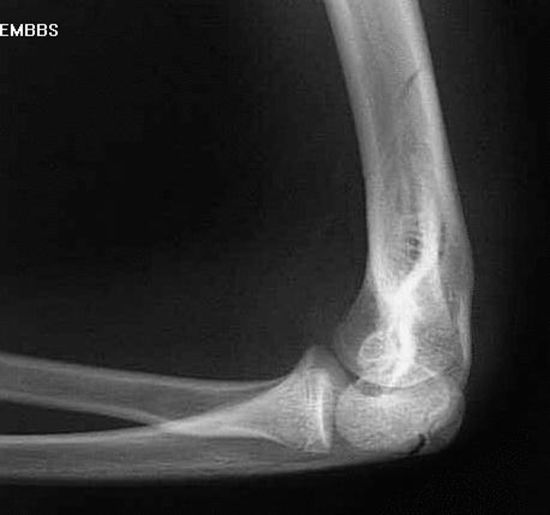

肘关节脱位

肱骨髁上骨折